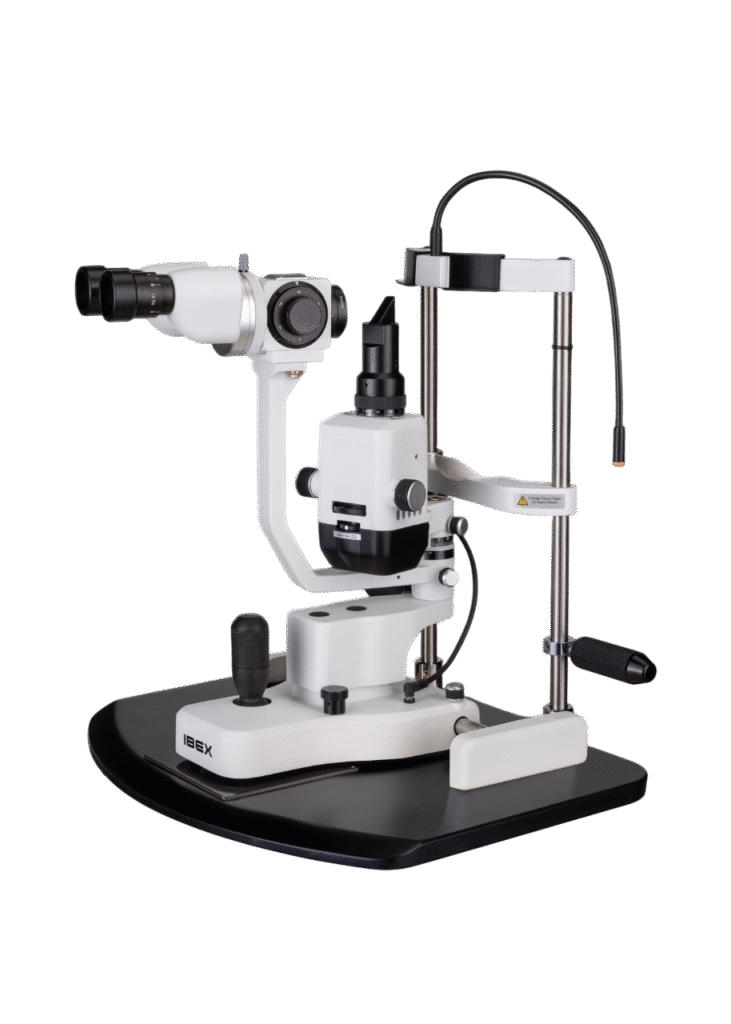

Opteon™ Slit Lamp Imaging + Meibography

Photos & Videos. Clinical Documentation. Patient Education. Reimbursement.

Illuminate your exams and transform patient engagement like never before. When patients see detailed images of their eyes, they gain a deeper understanding of their health and recognize the importance of compliance and follow-up care. Throughout development, our team saw firsthand the profound impact of imaging in the clinic—watching patients smile, express genuine appreciation, and embrace their health journey. That unforgettable experience remains the most rewarding part of our work.

Opteon was born and developed in the clinic, meticulously tested, and perfected through countless hours to ensure that it flows with your exam routine — delivering unmatched reliability and efficiency.

Pushing ahead, our imaging system includes our new, patent-pending Halo background light. Working with native slit lamp illumination, Halo delivers unparalleled clarity of the ocular adnexa. You’ll uncover details of the meibomian glands, acinar spaces, conjunctiva, lid margins, and lashes like never before.